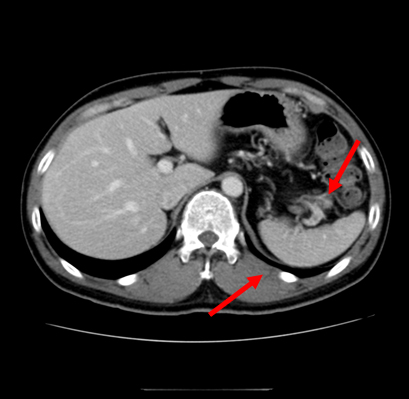

No. 154 症例4:30歳代男性

【画像所見まとめ】

• 脾多発腫瘤、脾門部多発リンパ節腫大

• 腸管内に錠剤あり

• 肝、脾

• 腸溶錠から既往歴を推測し、背景疾患の有無を確認する。